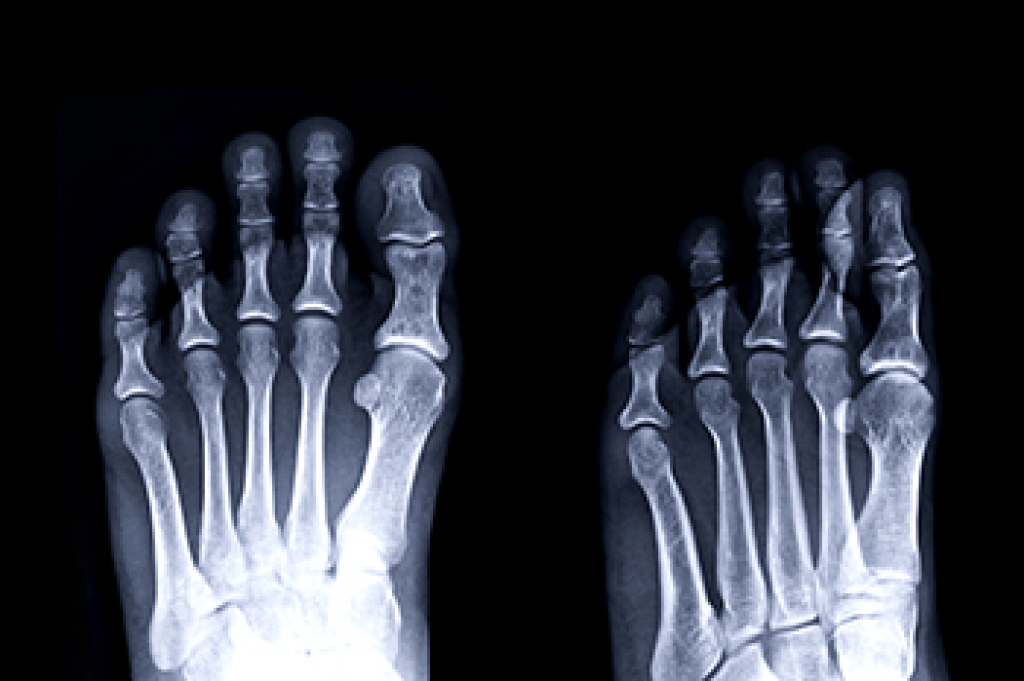

Stress fractures are small cracks in bones that often stem from repetitive motions. Stress fractures are common injuries among athletes, runners, or individuals with weakened bones due to poor nutrition or medical conditions. Symptoms of stress fractures include enduring pain during physical activity, tenderness, and mild swelling that primarily occurs in the lower leg and foot. Diagnosis of stress fractures can be elusive as an X-ray may be unable to detect the hairline cracks in the bones. In those cases, a podiatrist can employ an MRI or a bone scan for confirmation. Treatment typically entails rest, immobilization using casts or braces, and, in rare instances, surgery. Early detection and intervention can help to avert further complications and ensure a smoother recovery process. If you believe you may have developed stress fractures in your feet, it is suggested that you make an appointment with a podiatrist for thorough testing and treatment options.

Stress fractures are the result of repetitive force being placed on the bone. Since the lower leg and feet often carry most of the body’s weight, stress fractures are likely to occur in these areas. If you rush into a new exercise, you are more likely to develop a stress fracture since you are starting too much, too soon. Pain resulting from stress fractures may go unnoticed at first, however it may start to worsen over time.